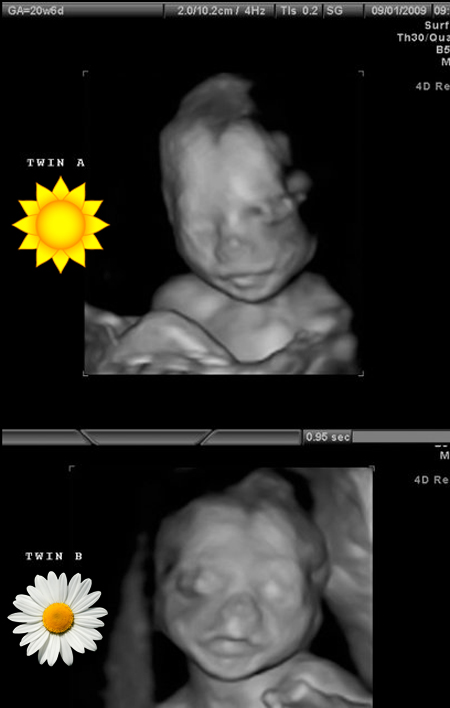

September 1st, 2009. Our ultrasound tech, Sureka, said the babies were looking really good that day, so against standard protocol, she pulled out the 3-D ultrasound wand and took some pictures for us of our beautiful, healthy, identical looking babies. What a gift those pictures were then. And even more so now.

Love, love, love, LOVE you! And I love the pictures of your beautiful babies, so wonderful that you have those!

Tova, every time I read your posts you make me cry. I love that you shared these beautiful pictures of your girls too. Thank you for being brave and representing the muchness and helping us all find and get ours back. You are amazing.